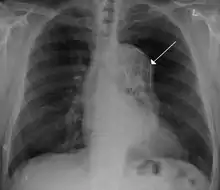

![]() أم دم الأبهر الصدري مع سهم يشير إلى الجانب الوحشي من شريان الأبهر. أم دم الأبهر الصدري مع سهم يشير إلى الجانب الوحشي من شريان الأبهر. | |